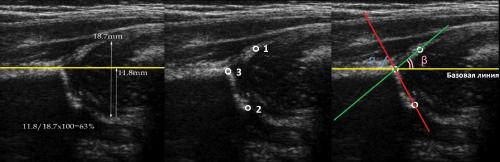

На первом этапе тазобедренный сустав сканируют в продольной плоскости. Проводят основные линии, измеряют костное покрытие головки, расстояние от лобковой кости до головки, ∠α и ∠β, а также определяют тип строения по Графу.

На втором этапе оценивают стабильность тазобедренного сустава сустава при пробе Барлоу-Ортолани. В нестабильном суставе костное покрытие головки уменьшается, а расстояние от лобковой кости до головки и ∠β увеличиваются.

Датчик располагают в проекции большого вертела параллельно поясничному отделу позвоночника. Найдите самое глубокое место вертлужной впадины. Отрегулируйте наклон датчика, чтобы линия тела подвздошной кости лежала строго горизонтально (2).

Линии костной (красная) и хрящевой (зеленая) крыши проходят через костный выступ, а так же начало Y-хряща и центр гиперэхогенного кончика суставной губы, соответственно. Степень развития костной крыши определяет ∠α, а хрящевой крыши ∠β.